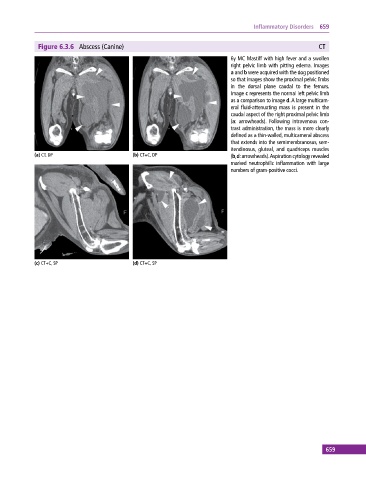

Figure 6.3.6 Abscess (Canine) CT

6y MC Mastiff with high fever and a swollen

right pelvic limb with pitting edema. Images

a and b were acquired with the dog positioned

so that images show the proximal pelvic limbs

in the dorsal plane caudal to the femurs.

Image c represents the normal left pelvic limb

as a comparison to image d. A large multicam-

eral fluid‐attenuating mass is present in the

caudal aspect of the right proximal pelvic limb

(a: arrowheads). Following intravenous con-

trast administration, the mass is more clearly

defined as a thin‐walled, multicameral abscess

that extends into the semimembranosus, sem-

itendinosus, gluteal, and quadriceps muscles

(a) CT, DP (b) CT+C, DP (b,d: arrowheads). Aspiration cytology revealed

marked neutrophilic inflammation with large

numbers of gram‐positive cocci.